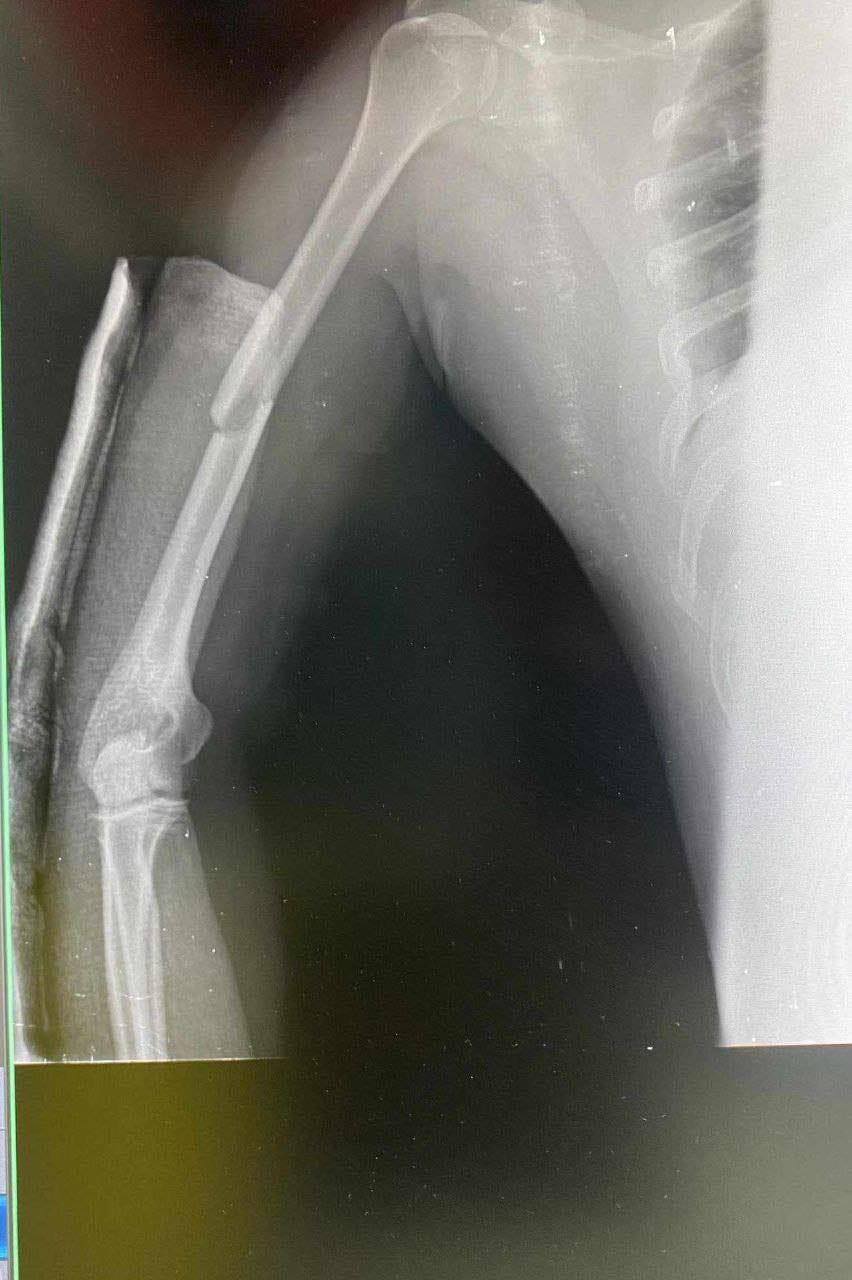

ខេត្តស្វាយរៀង ​៖​ មាន​ករណី​គ្រោះថ្នាក់​ចរាចរណ៍​ដ៏​រន្ធ.ត់​​​មួយបានកើតឡើង ​ខណៈលោកនាយ​រង​ផ្នែក​សណ្តាប់ធ្នាប់​នគ​បាល​ចរាចរណ៍​នៃ​អធិការដ្ឋាន​នគ​បាល​ក្រុង​ស្វាយ​រៀង​ម្នាក់​កំពុងឈរមើលសណ្តាប់ធ្នាប់នៅលើចិញ្ចឹមផ្លូវ​ជាតិលេខ១ ស្រាប់តែត្រូវ​​រថយន្តមួយគ្រឿងម៉ាកព្រូស ពណ៌ស បុ.កយ៉ាង​ពេញទំហឹង បណ្តាល​ឱ្យលោក​នាយ​រង​ផ្នែក​សណ្តាប់ធ្នាប់​ចរាចរណ៍​​រូប​នោះ​រង​របួស​ធ្ងន់ធ្ងរ បាក់ឆ្អឹងជំនីរ​ បាក់ដង​កាំបិត បាក់ដៃ​ម្ខាង ដាច់​ជង្គង់​ទាំង​សងខាង បាក់​ថ្គាម និង​ពក​ក្បាល​ធ្ងន់ធ្ងរ​សន្លប់​នៅ​និង​កន្លែង​គួរ​ឲ្យ​ស​ង្វេ​គ​​។​

ករណី​គ្រោះថ្នាក់​ចរាចរណ៍​ខាងលើ​នេះ​បាន​កើតឡើង​កាលពី​វេលា​ម៉ោង​៦​និ​១០​នាទី​ព្រឹក​ថ្ងៃ​ទី​៣០​តុលា​ ឆ្នាំ​២០២៣ នៅ​ខាងកើត​ផ្លូវបំបែក​ជា​បួន​ (​លើ​ចិញ្ចើម​ផ្លូវជាតិ​លេខ​១)​ ត្រង់​ចំណុច​ខាង​មុខ​ហាង​លក់​ម៉ូតូ ស្ថិត​នៅ​ភូមិ​បាក់​រនាស់ សង្កាត់​សង្ឃ​រ័ ក្រុង​ស្វាយ​រៀង សមត្ថកិច្ច​ដាក់​ការ​សង្ស័យ​ថា ជន​បង្ក​មាន​ចេតនា ។​

បច្ចុប្បន្ន​ជន​រង​គ្រោះ​កំពុង​សម្រាក​ព្យាបាល​នៅ​មន្ទីរពេទ្យ​កាល​ម៉ែត្រ​រាជធានី​ភ្នំពេញ បាន​ធូ​រ​ស្រាល​បន្តិច ​ហើយ​គ្រូពេទ្យ​សង្ឃឹមថា​រួច​ផុត​ពី​គ្រោះ​ថ្នាក់​ដល់​អាយុជីវិត​ហើយ​៕​